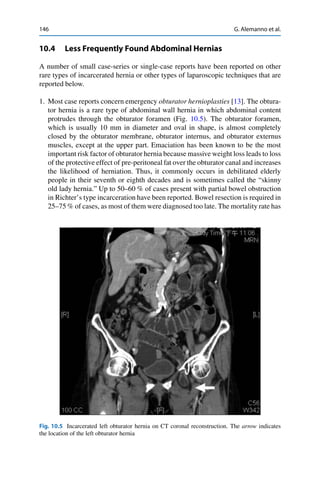

16 Emergency Laparoscopy:The Nurse’s Point of View 237 of complications may reduce morbidity and mortality. After surgery, nurse first detects and evaluates signs and symptoms of the three major vital systems (nervous, respiratory, and cardiovascular). Afterward, the accommodation and the comfort of the patient are ensured. At this point, nurse starts recognition, measurement, and recording of clinical parameters: blood pressure, heart and respiratory rate, oxime- try, glycemic index, pain, diuresis, characteristics and quantity of surgical drains (if placed), level of consciousness, body temperature, surgical wound, the presence of medical devices, and any symptoms reported by the patient. After LS particular importance covers the control of the presence of subcutaneous emphysema [36]. It is recommended to empty the urinary catheter and drains for precise postoperative monitoring. The nurse must verify the clinical documentation to check the surgical procedure and the type of anesthesia performed, any intraoperative problems, medications used, medical history and preoperative interventions performed, and not least the therapeutic prescriptions to be administered. All elements collected must lead the nurse to plan the subsequent appropriate care. Vital signs and clinical parameters of interest should be monitored every 1–2 h for at least the first 8 h. Moreover, nurse must continually check that the connections of the drainage pipes are correct and securely connected and the drains are working properly identifying significant bleeding or any appearance suggestive of complications (presence of bile, intestinal fluid, pus, urine air). Fundamental to the success of any model of team-based care is the skill, relia- bility, and expertise of the individual members that comprise the team, including nurses. Additionally, the definition of a standard of care and the adoption of shared protocols and therapeutic procedures (defined by surgical team) may allow rapid intervention for the management of major alterations and most common postoperative symptoms (hypertensive crisis, hyperthermia, nausea or vomiting, pain, hyperglycemia). The postoperative delirium is one of the most common adverse events after emergency surgery especially in the elderly [37].The surgical approach (laparoscopic versus open) does not seem to influence this condition. Nevertheless, in the emergency setting nurses are frequently facing with patients affected by cognitive dysfunction. In this regard, the use of screening tools, such as The Nursing Delirium Screening Scale [38], lead to early recognition. This way, the interventions required are readily performed reducing the risk of injury and accelerating the return to normality. 16.4.2 Surgical Rehabilitation After the initial 24 h, vital signs can be monitored every 4–8 h if the patient is stable. The incision and dressing should be monitored for the amount of drainage and signs of infection. The surgeon may order a dressing change during the first postoperative day; this should be done using sterile technique. The patient should be monitored for any evidence of potential complications, such as leg edema, redness and pain (deep vein thrombosis), shortness of breath (bronchopneumonia and pulmonary embolism), dehiscence and infection of the

• 247.

238 M. Rolfoet al. incision, or ileus (intestinal obstruction), heart problems. The surgeon should be notified immediately if any of these occurs. Particularly, in patients at higher risk of complication, rehabilitation exer- cises to prevent respiratory and thromboembolic complications should start early. When appropriate, preoperative education and maintaining previous levels of self- sufficiency increase the effectiveness of rehabilitative interventions [39]. The main objective of prevention is early mobilization from the bed [40]. If the patient is conscious, cooperative, and clinically stable mobilization can occur after only few hours after surgery, even after complex procedures [41]. Patients with limited mobility must be mobilized passively alternating on both sides several times a day, even for the prevention of pressure lesions, which is one of the main areas for action for nurses in this phase [42]. LS, even if performed in emergency, allows a rapid return to the levels of self-sufficiency when postoperative rehabilitation is rapid and constant [43]. Historically, the assumption of liquids and foods happens to the restarting of the intestinal functionality; nevertheless, this attitude was questioned by early rehabilitation programs in surgery having highlighted the absence of the benefit of fasting in various postoperative surgical procedures [41]. Few data are available about this aspect in emergency surgery, but a similar strategy should probably be chosen especially for minor procedures [44]. 16.4.3 Therapeutic Education: The Role of the Nurse The preoperative education is an important aspect of preparation for many surgical procedures. In particular, it has positive effects on fear [45] and anxiety [46] even prior to emergency surgery [47]. The contents of preoperative education may vary in different contexts, but generally include a presentation on the procedures and perioperative care, with respect to potential complications, management of the pain and other symptoms, device management, the mobilization, and respiration [48]. In the emergency setting, clinical conditions and degree of urgency may not enable a structured educational intervention. As previously reported [49], giving information just before surgery in urgency increases stress in anxious patients. In fact, education is best given at hospital admission. Nevertheless, therapeutic education on postoperative process is a high priority for patients and family members anticipating temporary changing needs as a result of the surgery. This stage of education usually happens preoperatively, preparing timely the patients at discharge. This way, the discharge is not an isolated event, but it becomes part of a process which begins at admission and actively involves patients and family during hospitalization [50]. However, for patients who underwent emergency surgery all the steps of this intervention are accomplished during the postoperative course. A well-structured educational plan is based on the quality of given information, to reassure patients that initial fears and anxieties are a normal part of the healing process. It has been demonstrated that this approach could positively affect expe-

• 248.

16 Emergency Laparoscopy:The Nurse’s Point of View 239 rience of postoperative pain, decrease preoperative state of anxiety, and promote exercise to prevent postoperative complications [51]. After surgery, nurse starts giving practical daily information as to the care of the surgical wound, both after laparoscopic and open surgery, diet, return to work, limits on activities, bowel movements, management of an eventual therapeutic regimen, and pain control. Before the discharge, other useful information should be given concerning the follow-up, such as the date, time, and location of their visits [52]. The best results are obtained associating oral information with other aids such as booklets or other information instrument. The delivery of written material has the advantage of ensuring a standardization of the educational process reducing the risk of the variability information based on different communication skills, knowledge, and resources of nurses. The multidisciplinary team (surgeons, anesthetists, nurses, nutritionists, dieti- tians, and respiratory therapists) collaborates in the educational process. In this scenario, the role of nurse is essential giving proper planning instructions and educating patient and family. 16.4.4 Pain Management The laparoscopic approach often results in lesser postoperative pain, shorter anal- gesia requirement, and earlier recovery. Nevertheless, in some cases early pain after laparoscopy can be comparable or even more severe than after open surgery. Pain intensity is maximal during the first postoperative hours and some patients need opioid analgesics to control it. Laparoscopy implicates insufflation of the abdominal cavity with carbon dioxide, and the remaining gas after pneumoperitoneum is one of the basics for postoperative pain, often described in the shoulder area and that it may persist for up to 72 h. However, pain after laparoscopic surgery is derived from multiple origins: nociceptive, incisional, and visceral pain; inflammatory pain in response to tissue trauma; and neuropathic pain in association with distension- induced neuropraxia. For this reason, a multimodal pain management protocol should be preferred. Moreover, persistent pain after laparoscopic surgery has also been reported. This condition could be partially explained by the influence of sociocultural and individual factors. Thus, these aspects should also be considered. Patient counseling on pain and pain management is important because it may increase the compliance and adherence to the selected analgesic treatments. More- over, reaching patients early, even before surgery, leads to influence psychological variables such as presurgical anxiety. In fact, the impact of psychological interven- tion on the prevention of persistent pain is yet to be demonstrated, but this approach seems to be promising in terms of outcomes in the acute postsurgical time period in combination with multimodal preventive analgesia [53]. As previously reported by Fernandez et al., an acceptance-based psychological intervention along with the usual presurgical protocol for a laparoscopic cholecystectomy will produce healthier reactions to postsurgical pain and will reduce anxiety, duration of postsurgical hospitalization, and demand of analgesics. Unfortunately, data on the management

• 249.